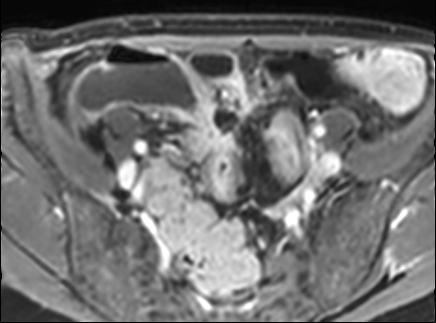

Rò

Đường xoang và đường rò là các biến chứng thường gặp ở bệnh nhân mắc bệnh Crohn.

Cả hai đều ngấm thuốc rõ rệt trên chuỗi xung T1W sau tiêm gadolinium.

Đường rò có thể biểu hiện dưới dạng cấu trúc phân lớp kiểu ‘đường ray tàu hỏa’ hoặc như một cấu trúc tuyến tính ngấm thuốc.

Đường rò có thể đi từ quai ruột này sang quai ruột khác, đến một tạng rỗng khác hoặc ra da.